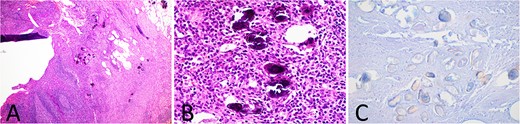

Subsequent histology demonstrated, in addition to features consistent with acute appendicitis, the presence of amorphous, round calcified deposits within the appendiceal wall and mesoappendix, representing Schistosoma ova (Fig. 2). The patient had no further symptoms and was prescribed a single dose of praziquantel for completion of therapy.

Histology slides of the appendix specimen; (A) (H&E stain, 20× magnification) features of transmural inflammatory infiltrate and serositis consistent with appendicitis and round calcified deposits within the appendiceal wall and mesoappendix; (B) (H&E stain, 400× magnification) amorphous, round, blue-black calcified deposits representing Schistosoma ova; (C) (modified Ziehl-Neelsen stain, 200× magnification) red-brown appearance of the Schistosoma ova shell.